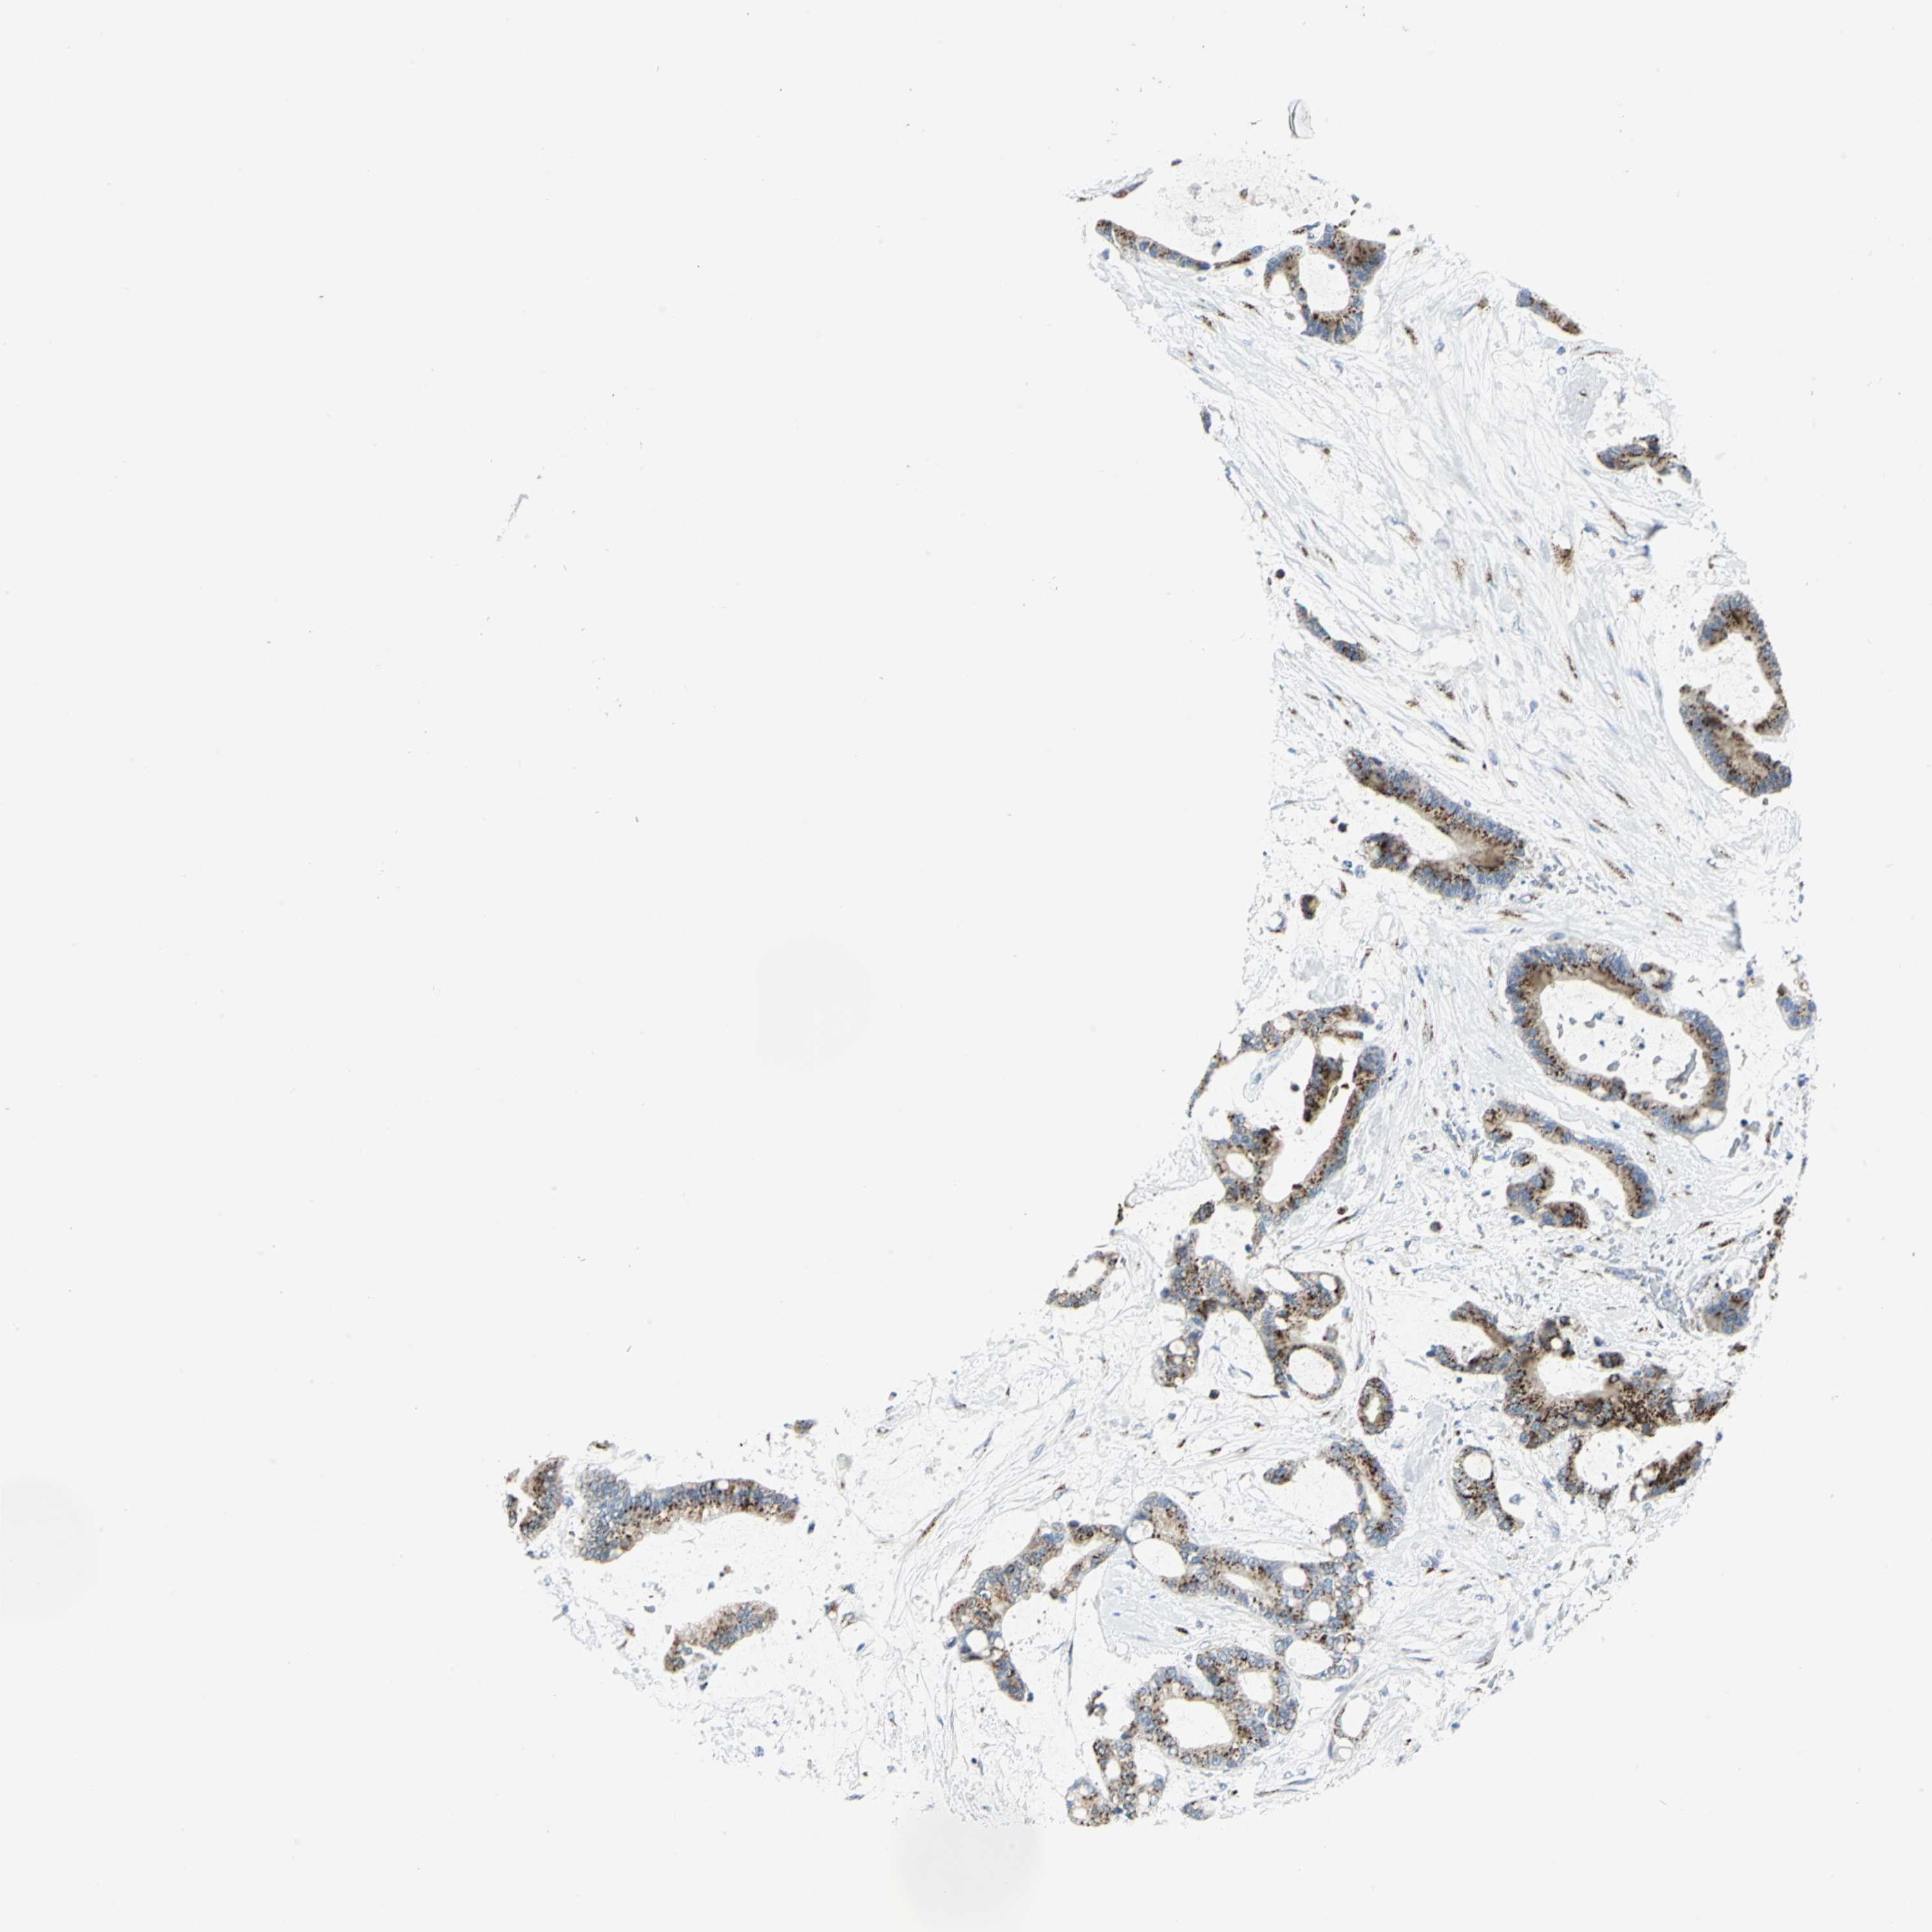

LIVER CANCER - Protein expressioni

A mouse-over function shows sample information and annotation data. Click on an image to view it in a full screen mode. Samples can be filtered based on level of antibody staining by selecting one or several of the following categories: high, medium, low and not detected. The assay and annotation is described here.

Note that samples used for immunohistochemistry by the Human Protein Atlas do not correspond to samples in the TCGA dataset.

Antibody stainingi

Antibody staining in the annotated cell types in the current human tissue is reported as not detected, low, medium, or high, based on conventional immunohistochemistry profiling in selected tissues. This score is based on the combination of the staining intensity and fraction of stained cells.

Each image is clickable and will lead to virtual microscopy that enables deeper exploration of all samples and also displays staining intensity scores, fraction scores and subcellular localization as well as patient and tissue information for each sample.

Antibody CAB006254

Staining

High

Medium

Low

Not detected

Intensity

Strong

Moderate

Weak

Negative

Quantity

>75%

75%-25%

<25%

None

Location

Nuclear

Cytoplasmic/membranous

Cytoplasmic/membranous,nuclear

Cholangiocarcinoma

Carcinoma, Hepatocellular, NOS